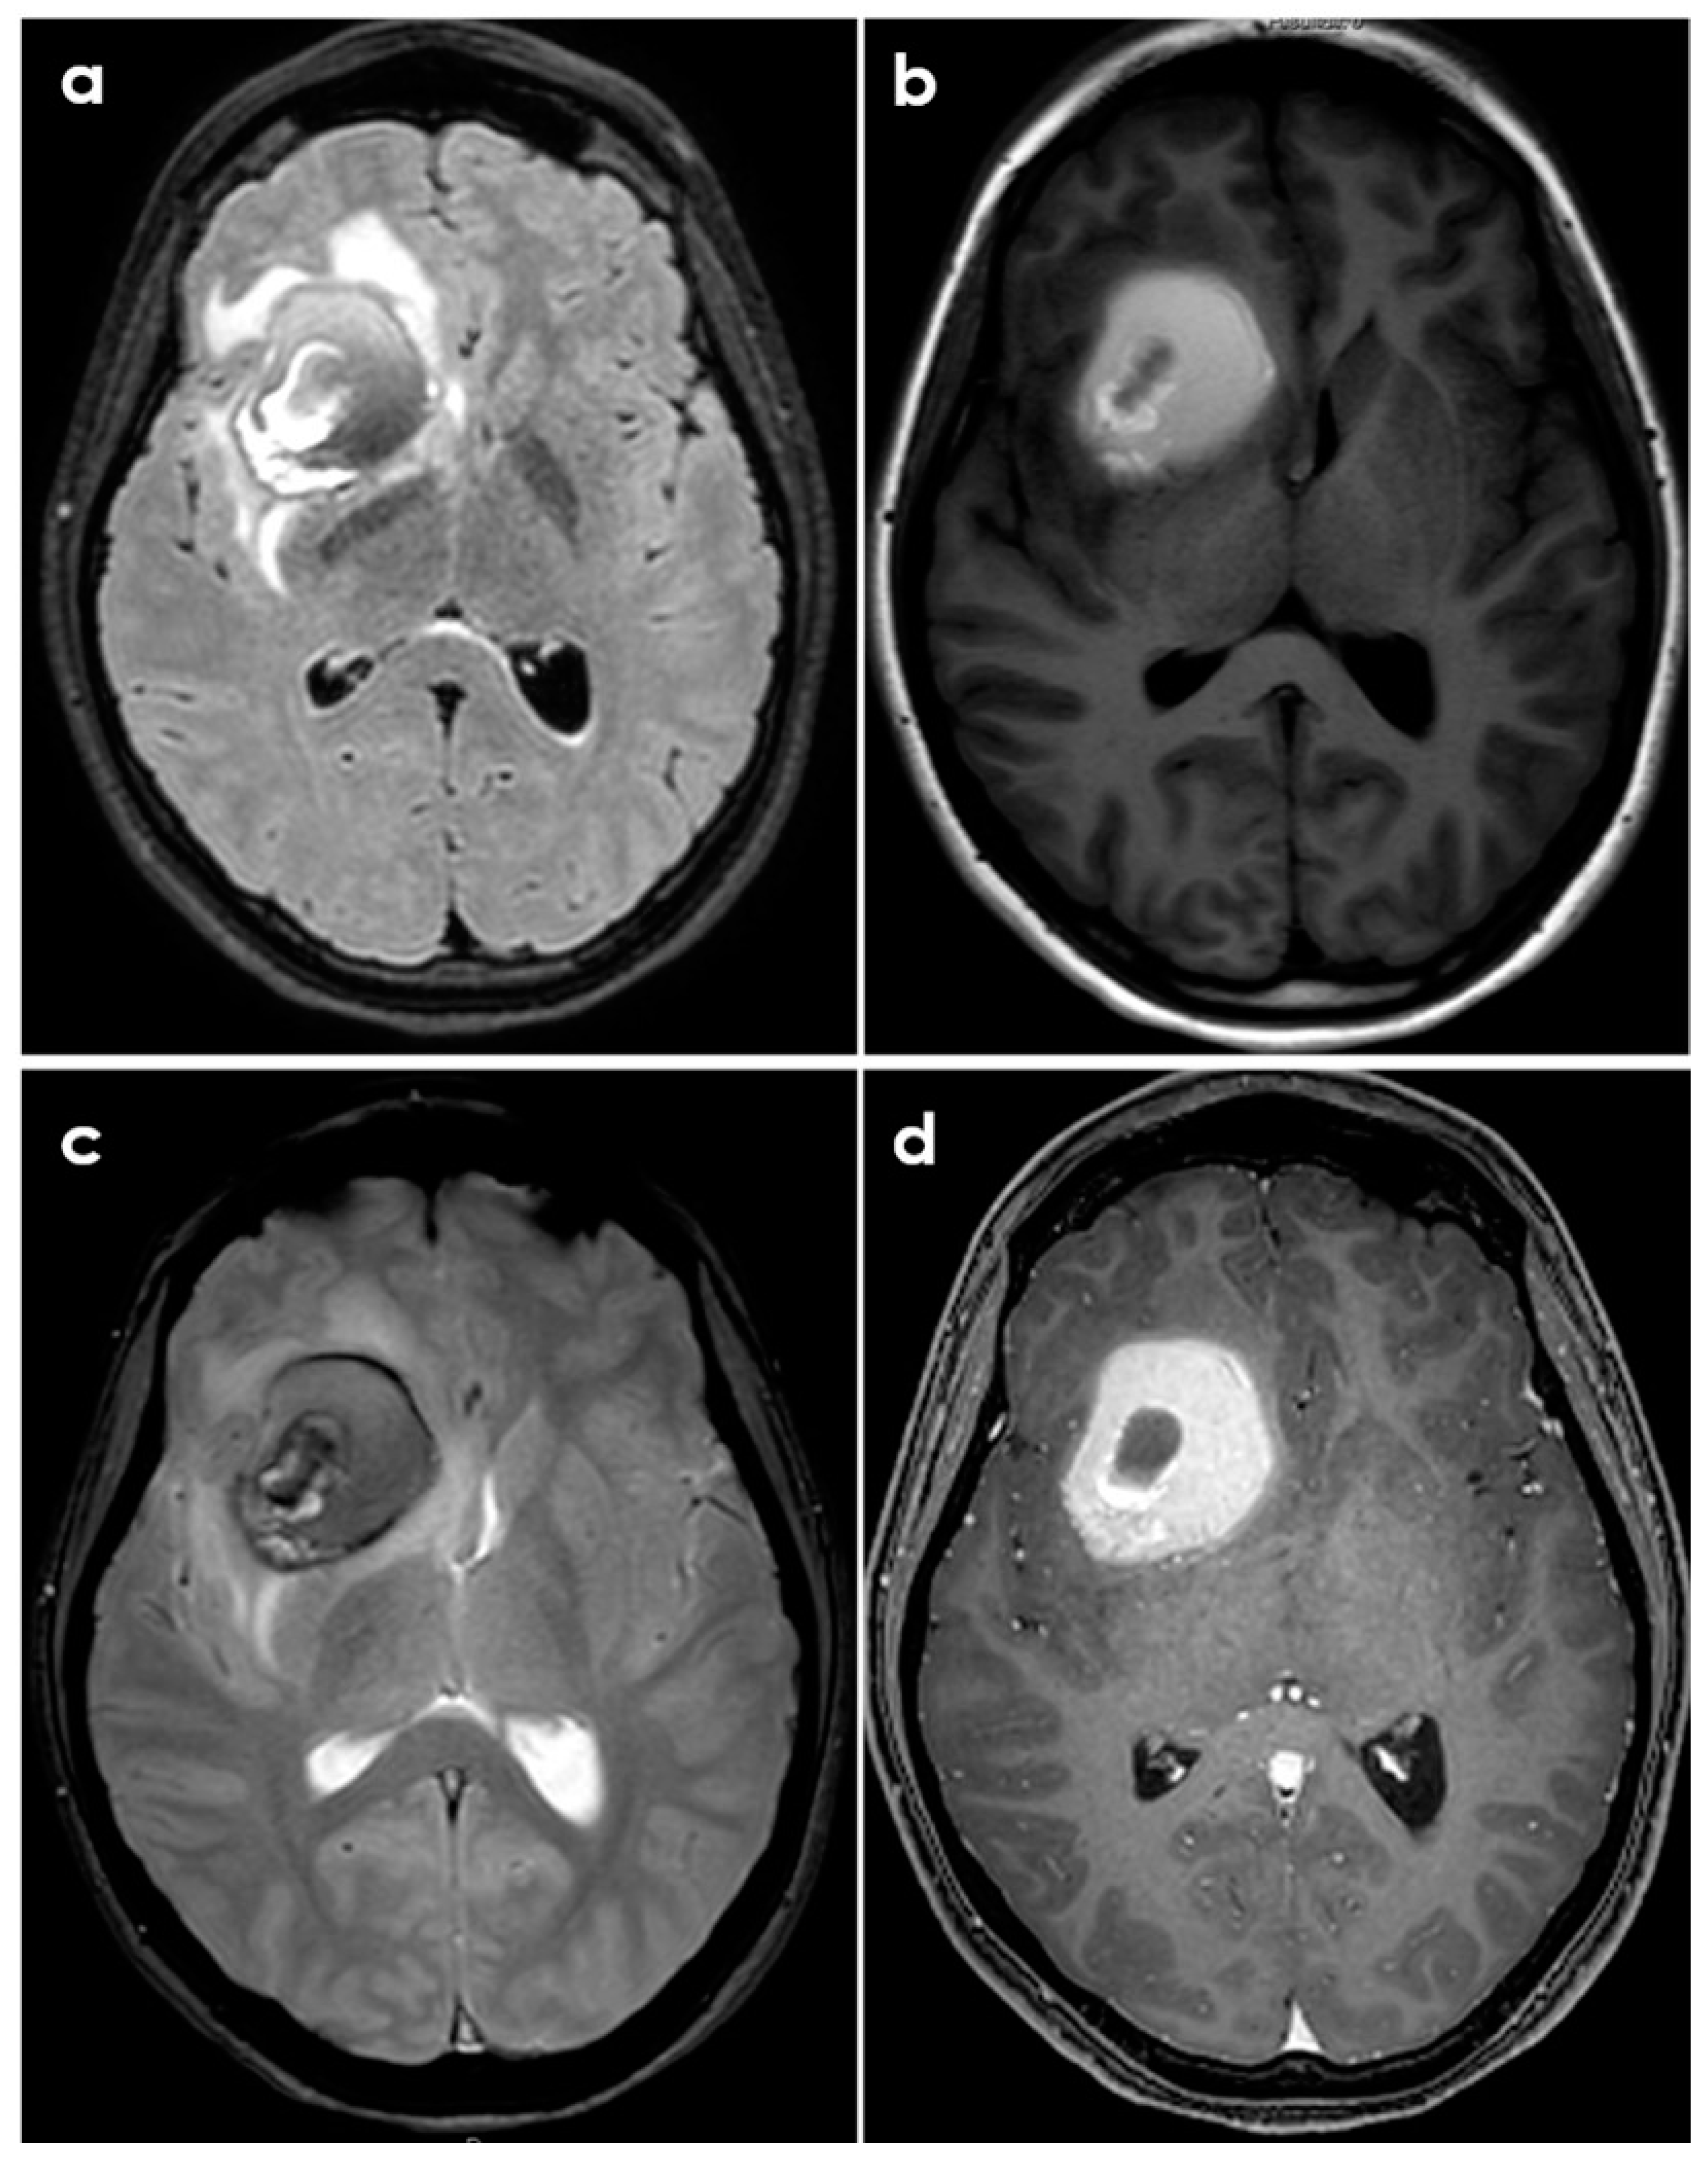

Sometimes PACNS-related ICH may not manifest with a hyperacute appearance on neuroimaging, as shown in Figure 2 and Figure 3.

Figure 3.

Brain MRI of the same patient described in Figure 2. Panel (a): axial fluid-attenuated inversion recovery (FLAIR) sequence, showing the rounded hematoma as a hypointense lesion and the surrounding edema as a hyperintense signal. Panel (b): T1-weighted axial sequence at the same level. Panel (c): gradient echo (GRE) sequence showing the various hypointensities of the hematoma components. Panel (d): post-contrast T1-weighted axial sequence showing the strong contrast enhancement of the hematoma in its peripheral ring.